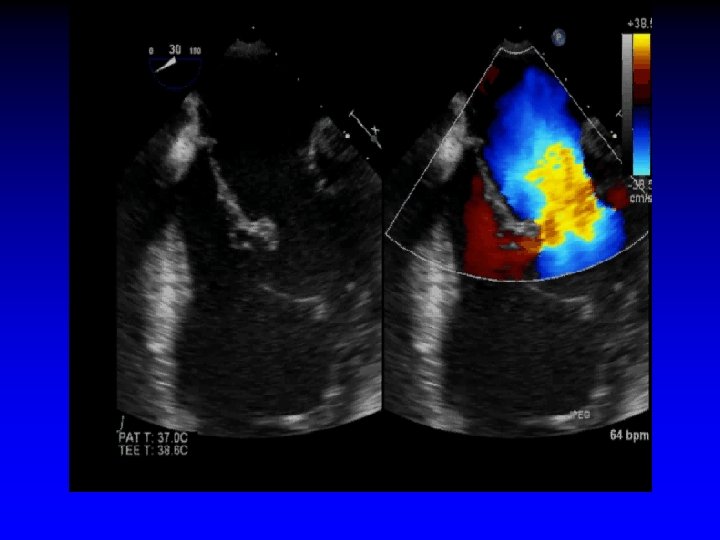

6. Grasping of the Leaflets PML AML

6. Assessment of Leaflet Capture Echo Guidance • Clip partially closed to secure insertion of leaflets into the clip • Carefully assess the grasp leaflets: - Adequacy of leaflet insertion - Resultant degree of MR

7. Post-Clip Placement Assessment Echo Guidance • Degeree of MR • Diastolic transmitral gradient • Achievement of double orifice Then, close the clip incrementally under echo-guidance